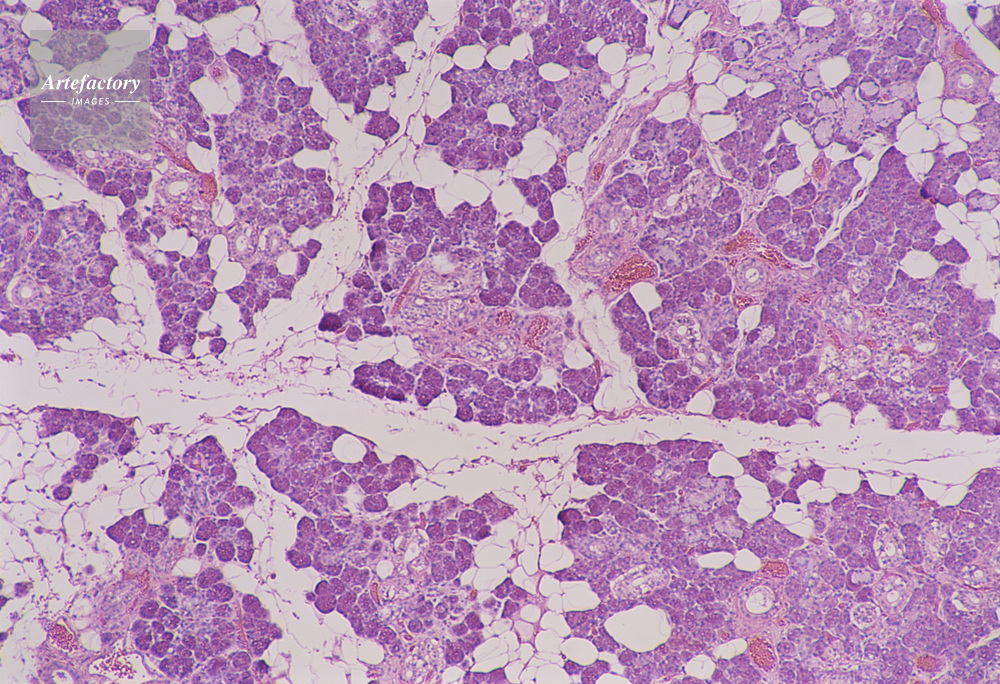

| キャプション | 唾液線管,人間,40倍, | 制限事項 | ||